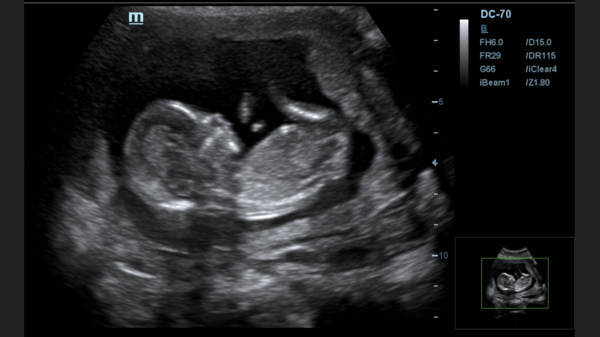

TheLemonBear · 18/05/2024 17:14

Hi, had my scan yesterday.. 12 weeks exactly.. can anyone see a nub? Or do the skull theory?

thanks

Skull theory